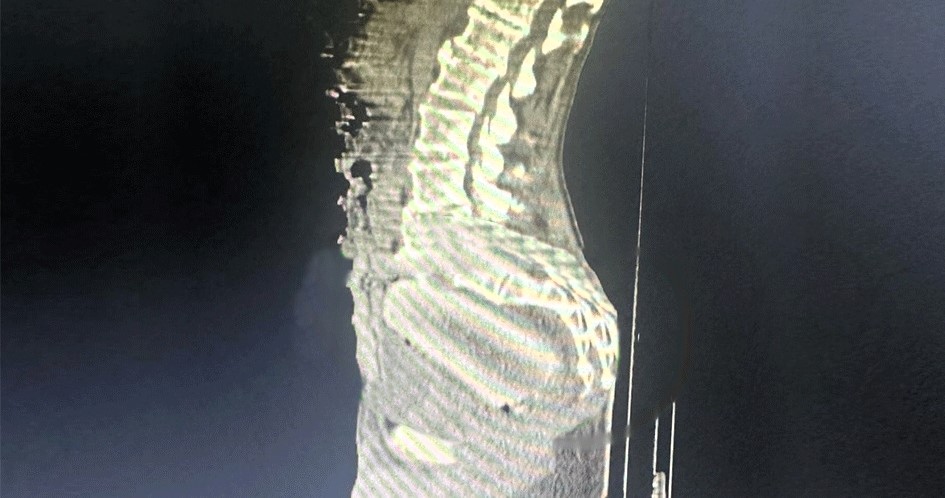

An image from an X-ray showed it was wedged deep inside the man’s rectum.